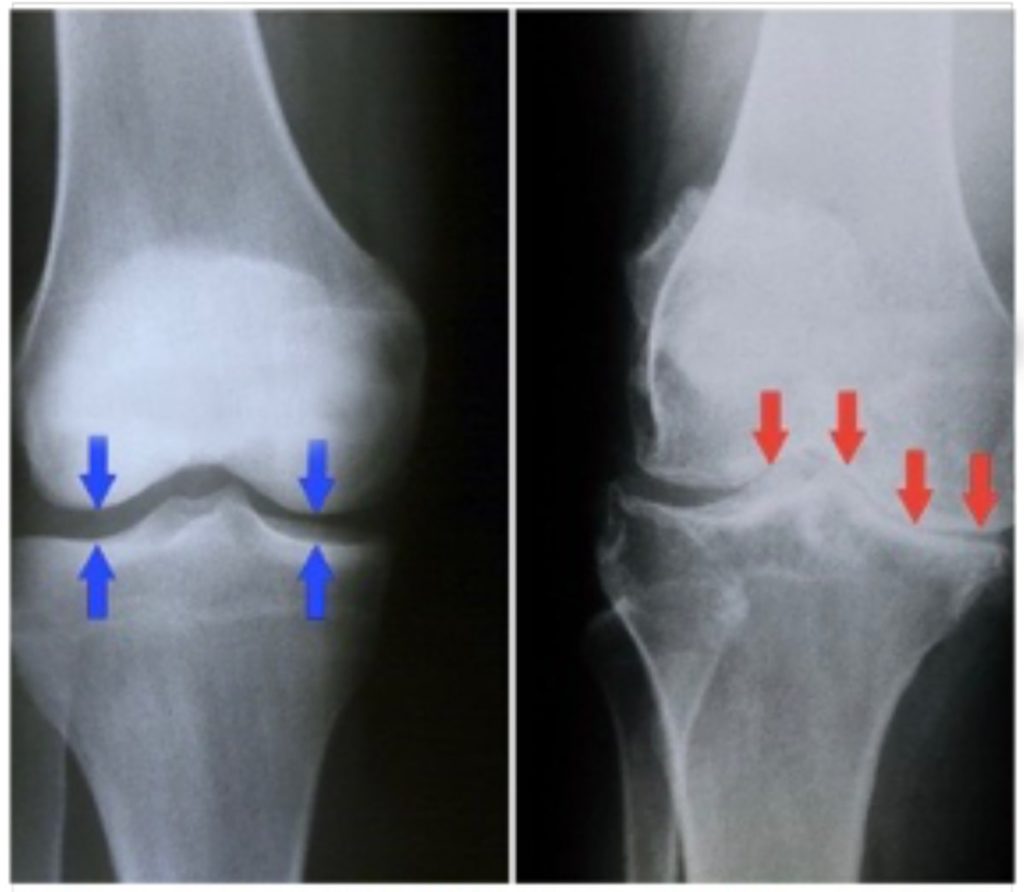

La osteoartritis se produce cuando el cartílago que amortigua los extremos de los huesos en las articulaciones se deteriora progresivamente. El cartílago es un tejido firme y resbaladizo que permite un movimiento articular prácticamente sin fricción.

Eventualmente, si el cartílago se desgasta por completo, el hueso se rozará con el hueso.

A menudo se habla de la osteoartritis como una enfermedad de 'desgaste natural'. Y además de la descomposición del cartílago, la osteoartritis afecta toda la articulación. Provoca cambios en el hueso y el deterioro de los tejidos conectivos que mantienen unida la articulación y que unen el músculo al hueso. También provoca la inflamación del revestimiento de la articulación.